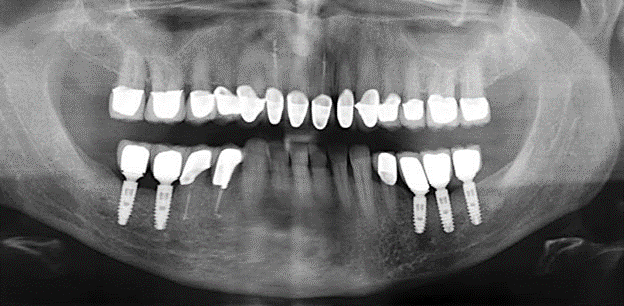

Abb. 1: Panoramaschichtaufnahme des Ausgangsbefundes im Jahr 2004.

Eine 52­-jährige Patientin stellte sich nach Zahnverlust im 3. Quadranten erstmals 2004 vor. Sie hatte den Wunsch nach einer prothetischen Neuversorgung. Im Rahmen der parodontologischen und radiologischen Diagnostik zeigte sich ein ausgeprägter parodontologischer Behandlungsbedarf. Die Zähne 48, 28, 27 zeigten zudem eine infauste Prognose und wurden entfernt (Abb. 1). Nach der erfolgreich abgeschlossenen systematischen PAR­Therapie wurde eine festsitzende implantatprothetische Versorgung mit Insertion von fünf Implantaten in Regio 35, 36, 37 und 46, 47 durchgeführt. Die prothetische Versorgung der natürlichen Zähne erfolgte mit verblendeten Zirkonoxidkeramikkronen, die Implantate wurden mit zweiteiligen individuellen Zirkonoxidabutments und ebenfalls verblendeten Kronen aus einer Zirkonoxidkeramik versorgt (Cercon base colored, Dentsply Sirona Lab). Die definitive Insertion der prothetischen Versorgung erfolgte im Jahr 2005.

Im Rahmen der Zehn­Jahres­Kontrolle zeigten sich keine Hinweise auf einen fortschreitenden parodontalen Attachmentverlust oder einen periimplantären Knochenverlust (Abb. 3).

Abb. 3: Panoramaschichtaufnahme nach einer prothetischen Funktionsperiode von zehn Jahren.